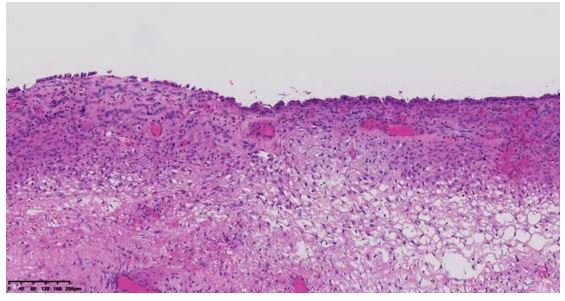

Following admission, the patient immediately underwent laparoscopic exploration. Intraoperatively, approximately 300 mL of dark-brown fluid was found in the pelvic cavity. The uterus was enlarged to the size of a 7-week gestation, smooth-surfaced, with multiple intramural fibroids (2.0–3.0 cm). The left fallopian tube was smooth; a left ovarian cyst was noted, 10×10 cm, with a smooth surface and a 1×1 cm rupture site leaking dark-brown fluid, but no active bleeding. The left cyst was densely adherent to the left fallopian tube, posterior and anterior uterine walls, and posterior leaf of the left broad ligament. Multiple right ovarian cysts (1–2 cm, smooth surface, intact capsule) were densely adherent to the posterior leaf of the right broad ligament; a millet-sized nodule and multiple yellow vesicular endometriotic lesions were found on the right fallopian tube. Both sacrouterine ligaments were contracted, with significant rigidity ("finger-like" on the left), and the left round ligament and adjacent soft tissue were firm, with marked retroperitoneal thickening. Part of the greater omentum was densely adherent to the anterior abdominal wall; yellow vesicular changes (3×3 mm) were noted along the left peritoneum near the round ligament. The bowel, mesentery, omentum, liver, spleen, and diaphragm appeared smooth with no obvious lesions; a flat black dot-like lesion (diameter ~4 mm) was observed on the peritoneum anterior to the liver, suspicious for endometriosis. During dissection, a cauliflower-like solid mass (4×3 cm) was found within the left cyst. As this was an emergency surgery, only the right adnexa was excised intraoperatively, with another elective surgery planned. Postoperative pathology: high-grade endometrioid carcinoma (endometrioid carcinoma, HEC) of the left side, with background evidence of endometriosis. Endometriosis was also observed on the serosa of the left fallopian tube. On postoperative day 1, repeat serum amylase was 75.4 U/L. Cytology from ascites was negative for tumor cells. Due to poor intestinal condition, a second staged surgery was planned.

Gynecological acute abdomen is an emergency primarily characterized by abdominal pain, often accompanied by other symptoms. Etiologies include malformations, infections, endometriosis (endometriosis, EMs), gynecologic tumors, surgical complications, or special circumstances, with peri- or postmenopausal cases largely attributed to tumors, trauma, or dysfunctions [1]. Acute abdomen progresses rapidly; failure to promptly and accurately diagnose and treat may result in shock and life-threatening conditions, representing surgical indications. Clinical symptoms, ultrasound, imaging, laparoscopy, and laboratory tests are the fundamental diagnostic approaches for evaluating causes of acute gynecologic abdomen [2]. This patient (46 years old) presented with abdominal pain mainly due to tumor etiology. Comprehensive assessment using ultrasound, CT, laparoscopy, laboratory testing, and postoperative pathology led to the diagnosis of right-sided high-grade endometrioid carcinoma on the background of endometriosis, with endometriosis also involving the left fallopian tube serosa. Ovarian endometrioid carcinoma (OEC) is an epithelial malignancy originating in the ovary with histopathological features similar to endometrioid carcinoma of the endometrium. OEC has a significant association with endometriosis [3,4], consistent with our case. Regarding laboratory tests, CA-125 and other tumor markers are routinely assessed, but serum amylase measurement also warrants clinical attention. An elevation of amylase in serum or body fluids has been associated with various neoplasms of non-pancreatic origin. Among cancer-related studies, amylase-producing tumors predominantly include cases of lung cancer, carcinoma, and multiple myeloma [5,6,7]. Serum amylase is considered a promising tumor marker. Amylase-producing tumors may present similarly to pancreatitis, as hyperamylasemia is common among such malignancies [8]. The predominant tumor amylase phenotype is often of the salivary type [9,10]. The pancreas and salivary glands are physiological sources of amylase. Normally, amylase is present in the digestive tract; its presence in the blood may indicate pancreatic or salivary gland cell injury—such as in pancreatitis, bile duct obstruction, sialadenitis, diabetic ketoacidosis, traumatic brain injury, or abdominal aortic aneurysm—causing release of amylase into the blood and resulting in elevated serum amylase [11]. Literature review reveals Jie et al. reported a case of carcinoma with intestinal involvement and elevated amylase; the diagnosis postoperatively was high-grade serous carcinoma, with amylase levels declining after surgery and chemotherapy [12]. Logie JJ et al. also reported a case of a woman in her 50s with abdominal distension and serum amylase exceeding 30 times the upper normal limit; postoperative pathology revealed high-grade serous carcinoma with metastatic spread. After chemotherapy and surgical treatment, serum amylase and CA-125 significantly decreased [13]. Gao et al. described a 46-year-old female with elevated amylase, ruling out other causes such as pancreatitis, finally diagnosed with advanced serous carcinoma [14]. In addition, Tohya T reported a 45-year-old patient with endometrioid adenocarcinoma associated with hyperamylasemia and liver metastases [15]. O'Riordan T reported a patient with serous surface carcinoma associated with abnormal amylase elevation [16]. Collectively, most reported cases are of serous carcinoma pathology; the current case, however, represents a rare instance of high-grade endometrioid carcinoma secondary to malignant transformation of an endometriotic cyst, accompanied by elevated amylase—an uncommon pathological type in previous reports. This suggests that carcinoma accompanied by elevated amylase may present in diverse pathological types. Several studies strongly suspect that tumor cells themselves produce amylase; however, further studies are needed to validate amylase as a significant tumor marker for endometrioid-type carcinomas. This case serves as supplementary evidence for clinical consideration, highlighting that in cases of acute abdominal pain with elevated serum amylase, malignancy should be considered in addition to acute pancreatitis. Carcinoma is a common gynecologic malignancy. CA-125 and CA-199 are standard tumor markers, but their specificity is limited. In clinical practice, large cystic tumors are frequently encountered, and imaging alone may not reliably differentiate between benign and malignant lesions. A novel marker would assist in determining tumor nature. For massive tumors—especially when presenting as acute abdomen requiring emergency surgery—serum amylase testing may offer further insight into the tumor's character and may inform the feasibility of large-scale screening for carcinoma.